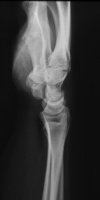

| She had progressive deterioration over two years with worsening pain and instability. |

| Eventually, she was treated with wrist fusion, distal ulnar resection and extensor carpi ulnaris tenodesis, and basal joint excision arthroplasty with split abductor pollicis longus anchovie interposition and ligament reconstruction - all through a single dorsal approach.: |